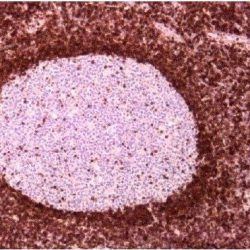

| Dilution | 1:50 |

| Staining | Cytoplasm |

| Control tissue | Tissue section from chromophobe carcinoma of the kidney |